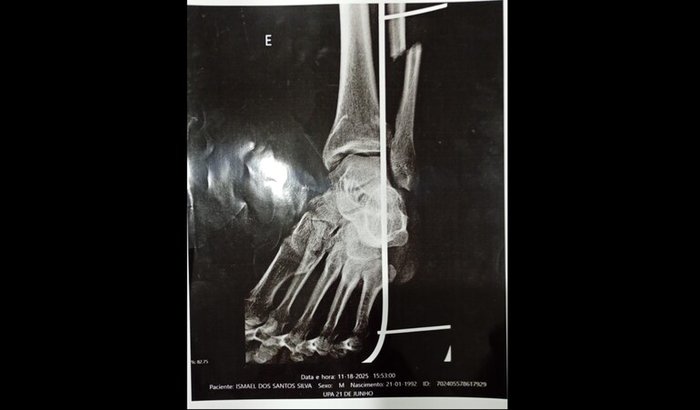

Pessoal eu sofri um acidente e infelizmente quebrei a fíbula e minha recuperação é de 3 há 4 meses .